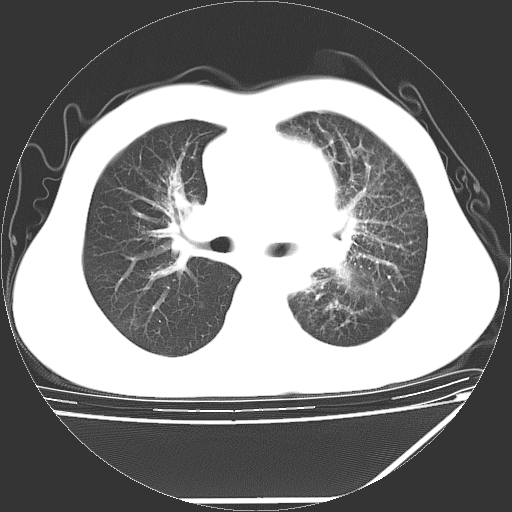

男,13岁,咳嗽、咳痰伴发热一周。

纵隔多发肿大淋巴结,部份有融合改变。双肺血管气管束增厚,以肺门为中心向外周散发,以左肺下叶为明显。考虑淋巴瘤可能性大。不除外原发综合征。

中上纵隔见多枚淋巴结肿大,部分相互融合成团片,左肺门增大,上叶支气管变窄,左肺支气管血管束增粗,可见磨玻璃样影。临床“男,13岁,咳嗽、咳痰伴发热一周。”首先考虑:淋巴瘤可能性大!

左肺野见淡片状影,病因整体多考虑结核

单纯看片子感觉左侧肺通气不畅,而不像肺内病变引起的纵隔病变。而且纵隔及左肺门都有淋巴结增大。首先还是考虑一下结节病,不排除淋巴瘤!!!